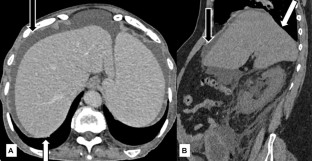

Bare area sign

Indiran, V., Kokilavani, J. Bare area sign. Abdom Radiol 44, 2674–2675 (2019). https://doi.org/10.1007/s00261-019-02007-1